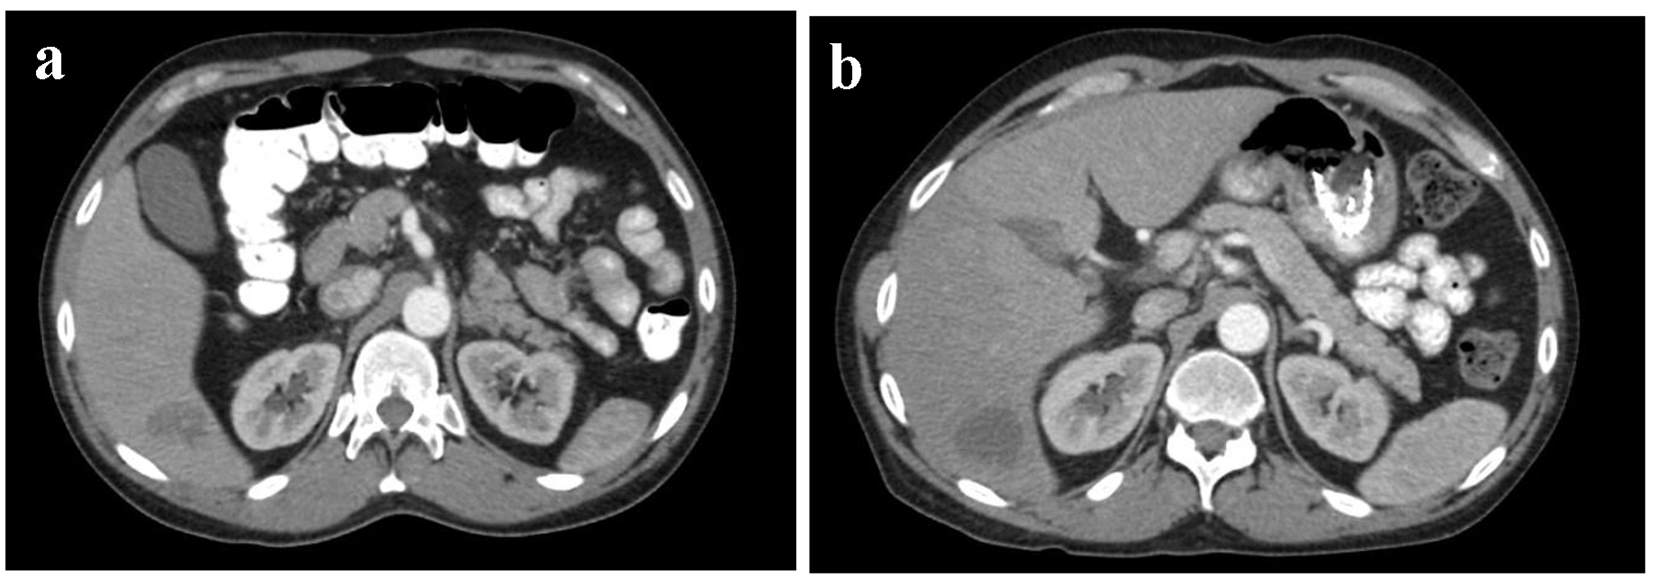

Initial imaging included computed tomography (CT) with oral and intravenous (IV) contrast of the chest which illustrated a posterior mediastinal soft tissue mass with necrosis measuring 6.0 × 8.8 cm abutting but not encasing the distal thoracic esophagus (Fig. 1a) [4]. Two prominent hypodense lesions were localized in the right posterior hepatic lobe measuring 2.6 × 2.8 × 2.9 cm and the medial segment of the left hepatic lobe measuring 1.6 cm in diameter (Fig. 2a) [4].

Figure 1. (a) Sagittal section of CT thorax with oral and IV contrast measuring posterior mediastinal mass prior to chemoradiation with dimensions of 6.0 × 8.8 cm. (b) Sagittal section of CT thorax with oral and IV contrast of posterior mediastinal mass after 10 cycles of CVD. Tumor size decreased to 5.5 × 3.0 × 4.0 cm.

The patient completed 10 cycles of chemotherapy and experienced a gradual improvement in his back pain, weight, appetite, swallowing, and performance status throughout treatment. Follow-up CT scans after the 10th cycle showed near complete response of the tumor and a decrease in size of the hepatic lesions. CT scan with IV and oral contrast measured the mediastinal mass to be 5.5 × 3.0 × 4.0 cm (Fig. 1b) [5]. The posterior right hepatic lobe lesion decreased in size to 2.6 × 2.8 × 2.9 cm, and the left hepatic lobe lesion completely resolved (Fig. 2b) [5]. These interval decreases in the hepatic metastasis corresponded to a partial response per response evaluation criteria in solid tumors (RECIST) criteria [6]. The patient finished a total of 12 cycles of chemotherapy with subsequent resolution of the primary mass and the hepatic lesions, thus corresponding with a complete response per RECIST criteria.

To our knowledge, this is the first reported case of combination CVD therapy and Y90 radioembolization for metastatic malignant paraganglioma. Our patient thus far has demonstrated remarkable clinical and radiological improvement with 10 cycles of the CVD regimen. Follow-up CT scans demonstrated a progressive decrease in tumor size throughout chemotherapy cycles. The decrease in size of the posterior mediastinal mass is likely attributed to a similar chemotherapy schedule as demonstrated previously in prior studies [9, 10]. The patient has demonstrated a decrease in the dominant metastatic liver lesions shortly after radioembolization of both the right and left hepatic arteries (Fig. 2a, b). The RECIST criteria monitor the imaging response to treatment of solid tumors. By applying this model’s calculation to this case, we have calculated a 58% decrease in the patient’s metastatic liver lesions. This corresponds with a complete response per RECIST criteria [6]. The most recent imaging studies after 12 cycles of chemotherapy and localized radiation therapy with Y90 radioembolization have shown complete remission of the primary posterior mediastinal tumor as well as all hepatic lesions to date.